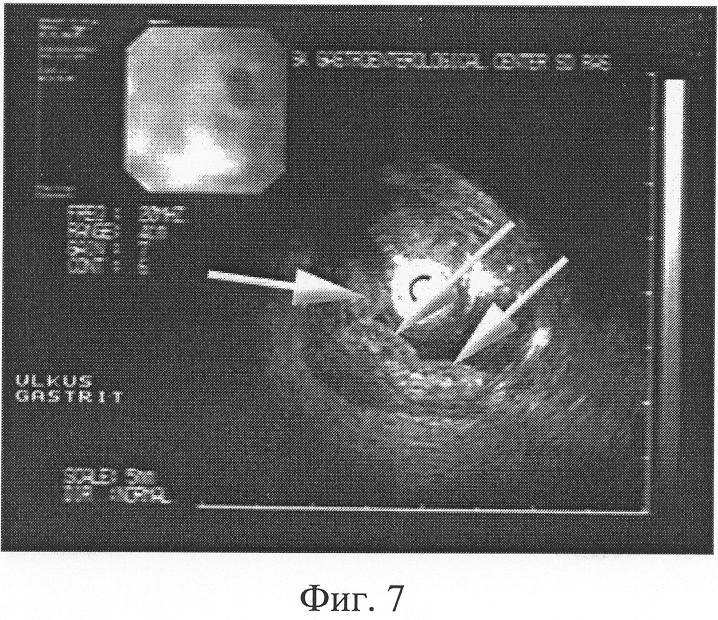

При наличии тонких выпрямленных складок, ширина которых в теле и антральном отделе желудка от 3 до 6 мм, по большой кривизне, в своде и синусе до 10 мм (Фиг.6), соотношении минимальной к максимальной высот желудочной складки от подслизистого слоя, приближающемся 1:1, наличии желудочных полей неправильной округлой или полигональной формы диаметром более 5 мм (Фиг.7) с расширенными бороздами диагностируют атрофический гастрит.

В результате проведенного исследования установлено, что слизистая пищевода обычной окраски. Кардия полностью смыкается. В желудке много светлой слизи. Слизистая желудка в антральном отделе бледно-розовой окраски, складки в теле и антральном отделе желудка истончены, выпрямлены, ширина складок в теле и антральном отделе желудка от 3 до 4 мм, по большой кривизне, в своде и синусе – до 6 мм (Фиг.6). Соотношение минимальной к максимальной высоте желудочной складки от подслизистого слоя приближается 1:1. Желудочные поля имеют неправильную округлую, полигональную форму, диаметром от 5 до 12 мм, с расширенными бороздами (Фиг.7). Взята биопсия из 5 участков слизистой тела и антрального отдела желудка. Привратник сомкнут, проходим. Луковица двенадцатиперстной кишки не деформирована, патологии со стороны двенадцатиперстной кишки нет. Заключение: Хронический атрофический гастрит. Гистологическое заключение №19876 от 28.05.04 г. – атрофический гастрит с признаками тонкокишечной дисплазии.

Фиг.6. Б-ная Л. 57 л. Эндоскопическая гастросонография. Тонкие выпрямленные складки желудка, ширина их в теле и антральном отделе от 3 до 4 мм, по большой кривизне, в своде и синусе – до 6 мм (обозначены стрелками). Соотношение минимальной к максимальной высоте желудочной складки от подслизистого слоя 1:1.

Фиг.7. Б-ная Л. 57 л. Эндоскопическая гастросонография. Желудочные поля (обозначены стрелками) неправильной округлой и полигональной формы, размером от 5 до 12 мм, с расширенными бороздами между ними.